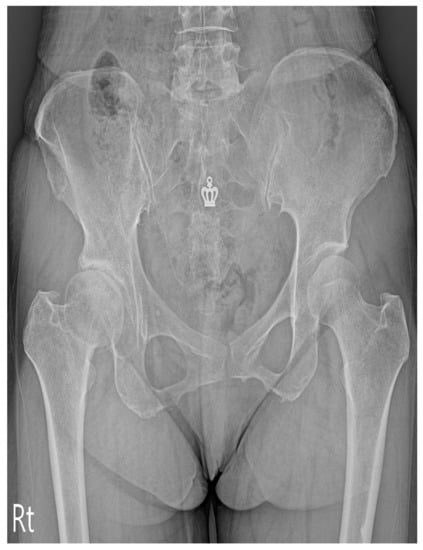

2. Case